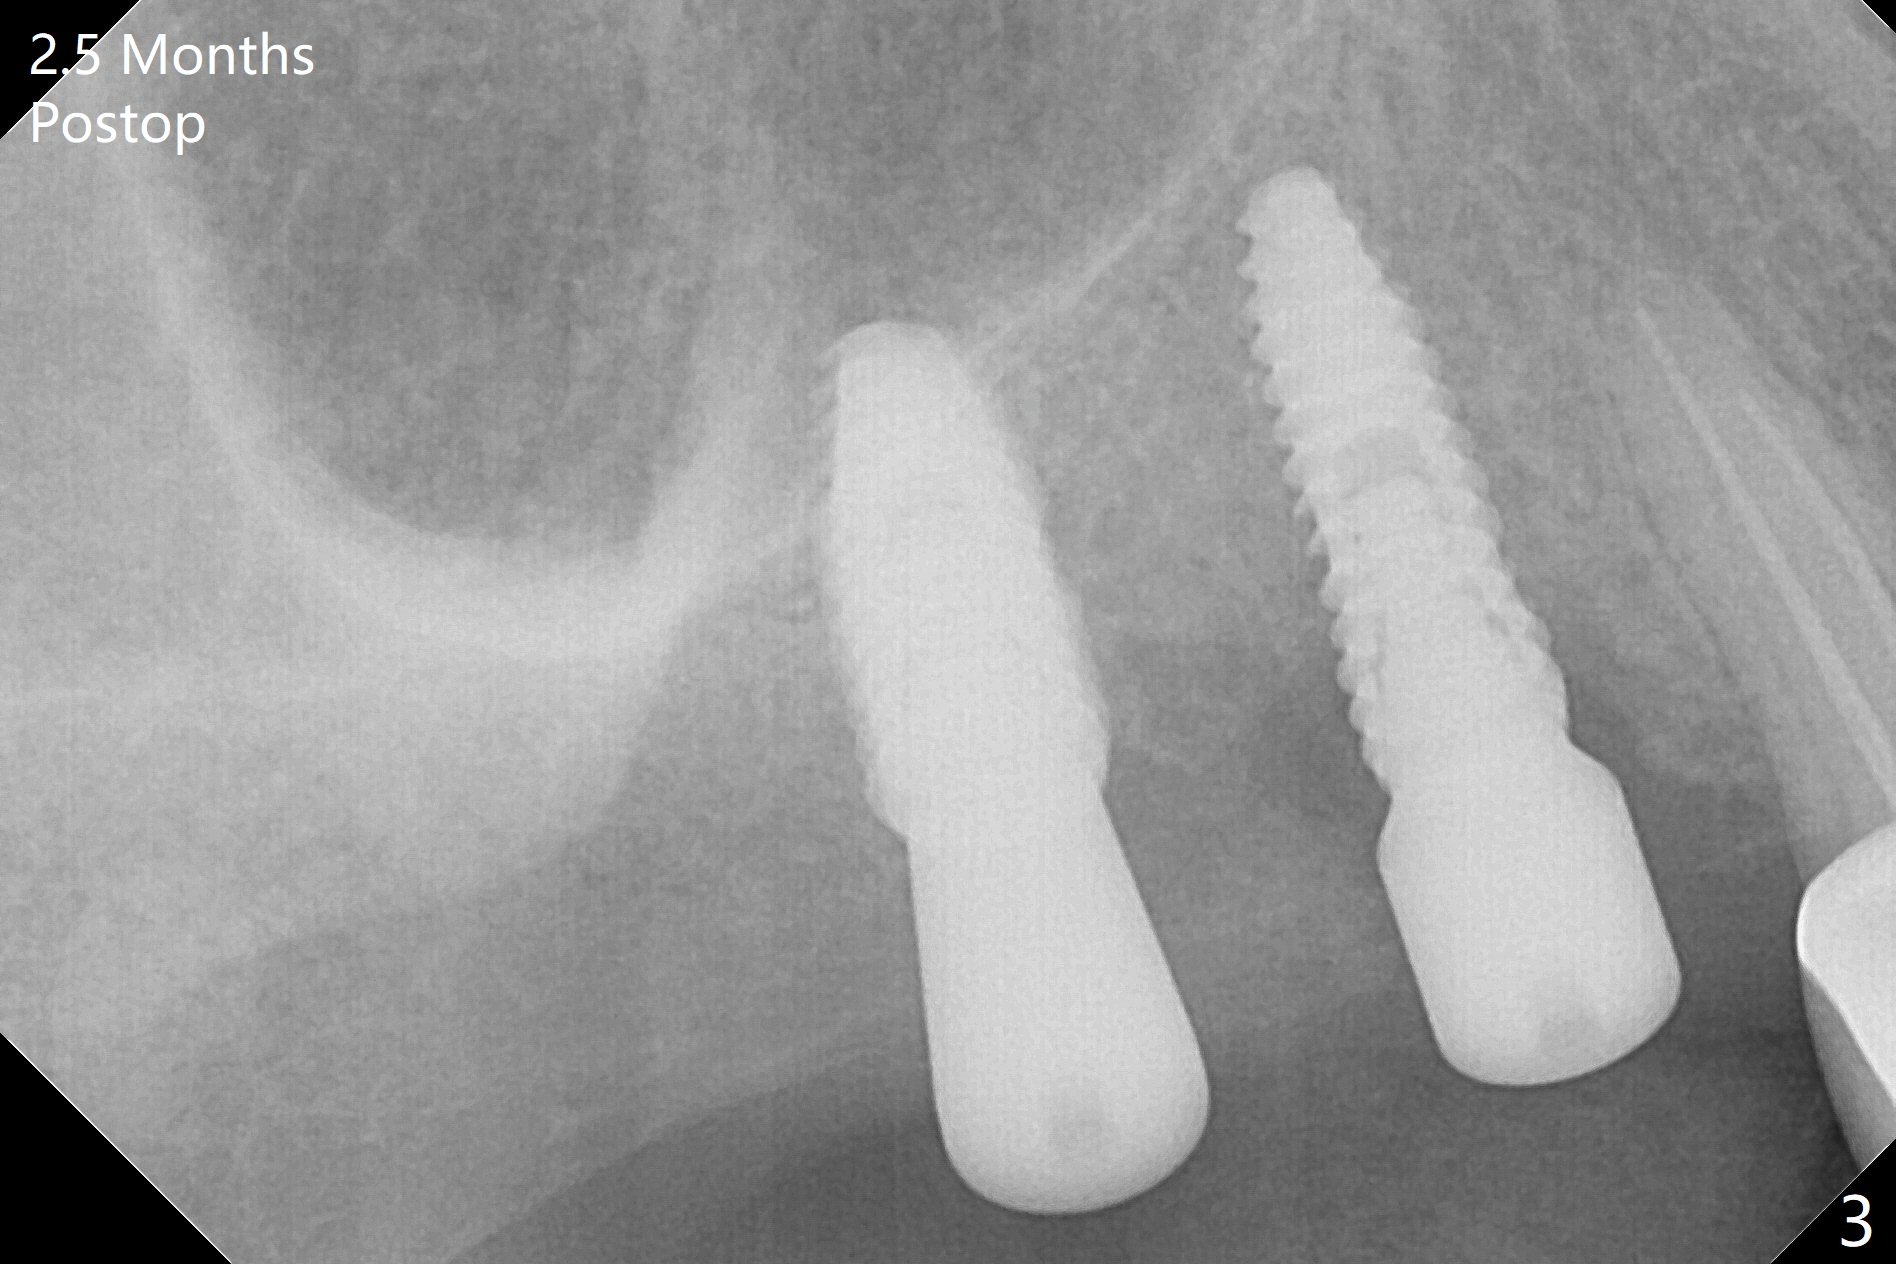

There is offset (10.5 mm) associated with #3 and 4 guided placement.  When #4 implant placement is done first with >20 Ncm, a fixture anchor pin cannot be engaged.  For anchorage purpose, can the implant be placed 1.5 mm shallower initially and then deeper later on (when #3 placement is done)?  In fact the insertion torque of #3 is less than 15 Ncm (Fig.1).  Narrow healing abutments are placed to reduce lateral micromovement.  Pain control is good with 1 carpule of Xylocaine with 1:100,000 Epinephrine.  The patient is pleased with much less postop discomfort than the 2 previous implant surgeries (#20 and 19).

There is history of mild postop hemorrhage for a few days postop, as related to healing laceration palatal to #4 (7 days postop, Fig.2).  There is mild discomfort when temporary splinted crowns are fabricated 2.5 months postop (Fig.3).